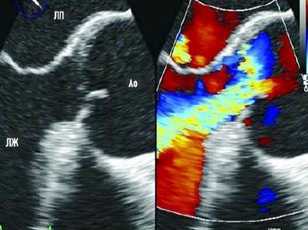

Трансторакальная ЭхоКГ проводилось по традиционной методике на ультразвуковом сканере экспертного класса с использованием мультичастотного микроконвексного датчика с частотой 2-4 МГц в продольном парастернальном сечении. В качестве верифицирующей методики применялась мультиспиральная компьютерная томография (МСКТ).

Помимо гипертрофии миокарда левого желудочка, склеротически измененных створок аортального клапана и наличия его недостаточности I степени, обращало на себя внимание расширение восходящего отдела аорты до 4,5-5,1 см (на различных уровнях) (рис. 1). Исследование средних отделов восходящей аорты (рис. 2) позволяло выявить нитевидную, невыраженно флотирующую структуру, расположенную по передней стенке аорты, формирующую истинный и ложный каналы аорты, которые более детально верифицировались в режиме ЦДК (рис. 3). В слепом участке ложного канала определялись тромботические массы. При исследовании из супрастернального доступа в области дистального отдела восходящей аорты и ее дуги лоцировался участок отслоения интимы (рис. 4). В остальных отделах аорты, доступных для визуализации, патологии выявлено не было. Таким образом, ультразвуковое исследование сердца позволило диагностировать расслаивающую аневризму восходящего отдела и дуги аорты (тип II по De Bakey). Проведенная МСКТ подтвердила данный диагноз (рис. 5).

Рис. 1. Эхокардиограмма больного Ж. Режим ЦДК. Парастернальная позиция по длинной оси.

1 - аорта, 2 - левый желудочек, 3 - межжелудочковая перегородка, 4 - задняя стенка левого желудочка, 5 - левое предсердие, 6 - регургитация на аортальном клапане.

Рис. 2. Эхокардиограмма больного Ж. Парастернальная позиция по длинной оси с фокусом на восходящий отдел аорты.

1 - отслоенная интима аорты, 2 - истинный канал аорты, 3 - ложный канал аорты, 4 - тромботические массы в слепом участке ложного канала аорты.

Рис. 3. Эхокардиограмма больного Ж. Режим ЦДК. Парастернальная позиция по длинной оси с фокусом на восходящий отдел аорты. Заполнение цветом просвета истинного канала аорты.